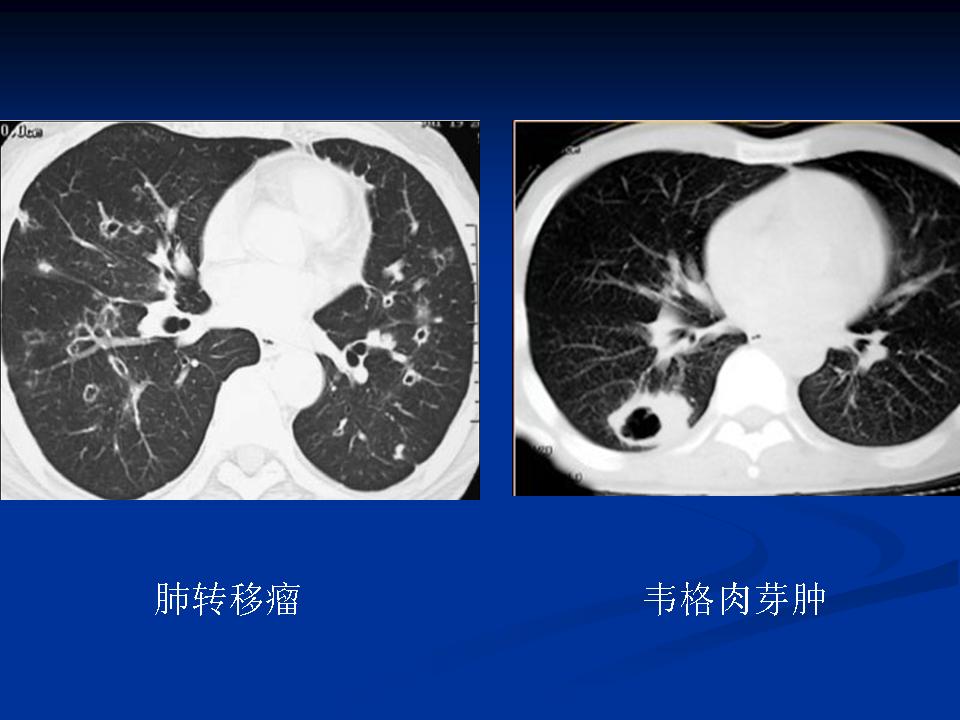

肺转移瘤与韦格肉芽肿影像鉴别